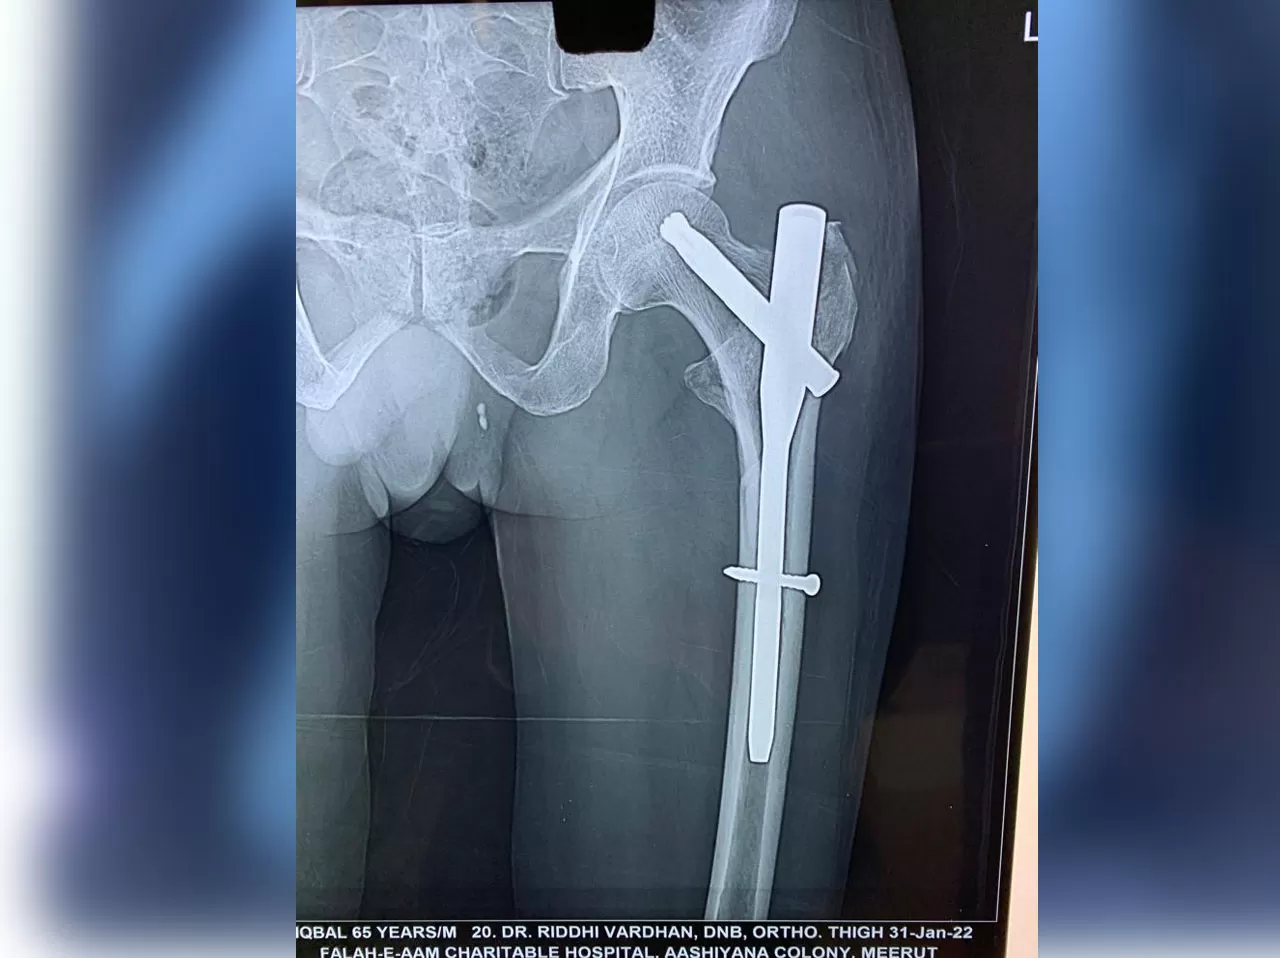

Mr. Iqbal

Name: Mr. Iqbal

Date of Operation: 31 Jan 2022

Age: 65 Years